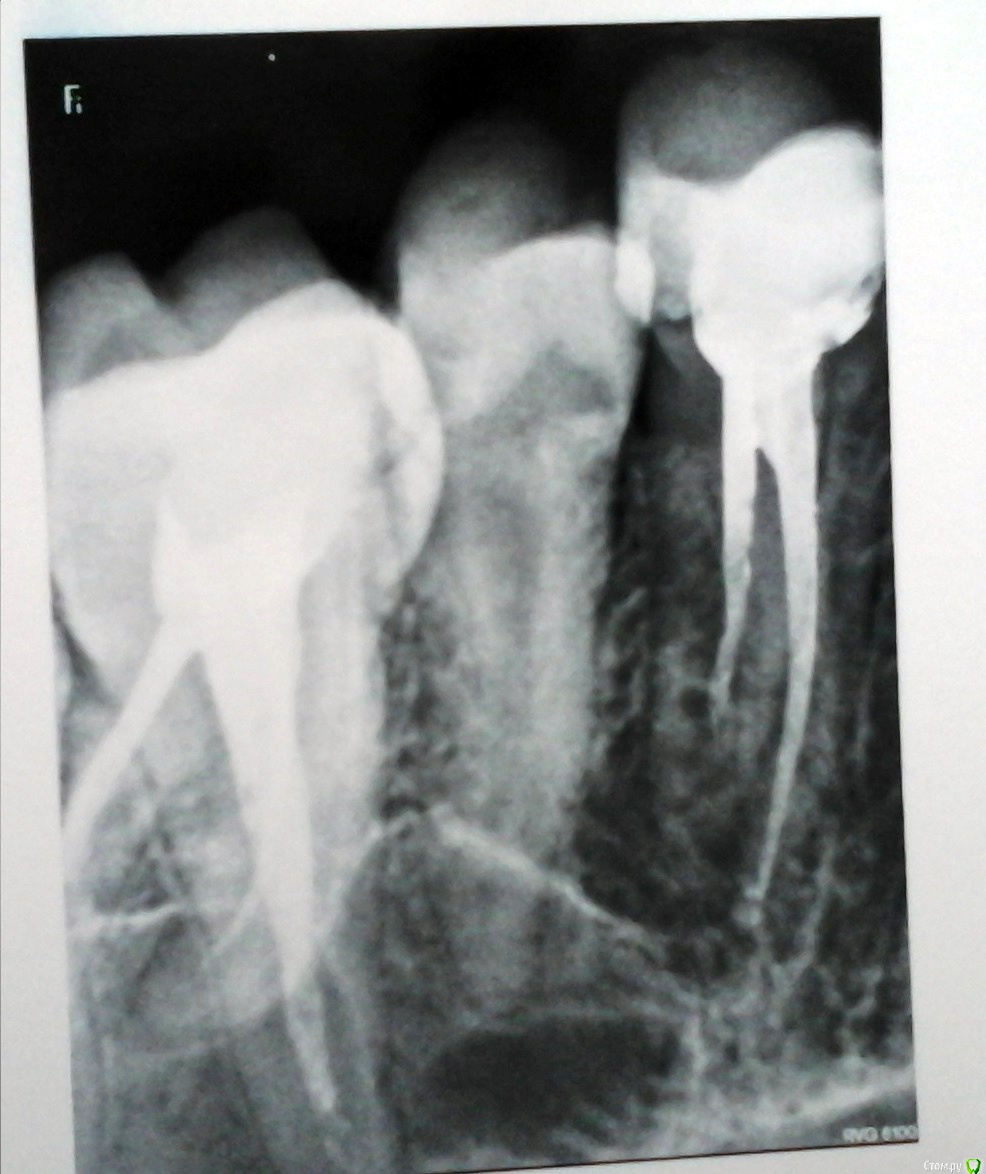

remenikomer Опубликовано 23 февраля, 2017 Поделиться Опубликовано 23 февраля, 2017 Подскажите, на что можно рассчитывать в такой ситуации?Проблема у жены, не у меня.Зуб после лечения, примерно года 3 назад. Сейчас немного припухла щека, боль при открывании рта. Жевать не больно. Решили сделать рентген. Клиники не работают в праздники. Врач, где делали снимок, сказал, что, много гноя и, возможно, долго не вытерпите (все праздники). Зуб, говорит, вряд ли спасти можно. А лечить она в этой клинике не хочет. Хочет в той же, где уже лечила.Подскажите, пожалуйста, что имеем, что ждать? Можно ли спасти зуб? И какая причина этому могла послужить, могло ли это случиться из-за плохого предыдущего лечения? Ссылка на комментарий

DmitrySH Опубликовано 23 февраля, 2017 Поделиться Опубликовано 23 февраля, 2017 Очаг воспаления вокруг одного из корней 4-го зуба. Но снимок лучше переделать, качество оставляет желать лучшего. 2 Ссылка на комментарий